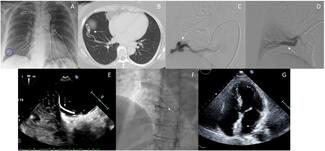

A 46-year-old man presented with bilateral lower extremity edema for more than 3 months. He had a history of bruising to the left abdominal area as a result of a motorcycle accident several years ago.

The authors report a patient experiencing transient ischemic attacks who was found to have patent foramen ovale and secondary septal pouch and who was treated successfully with an atrial septal defect occluder.